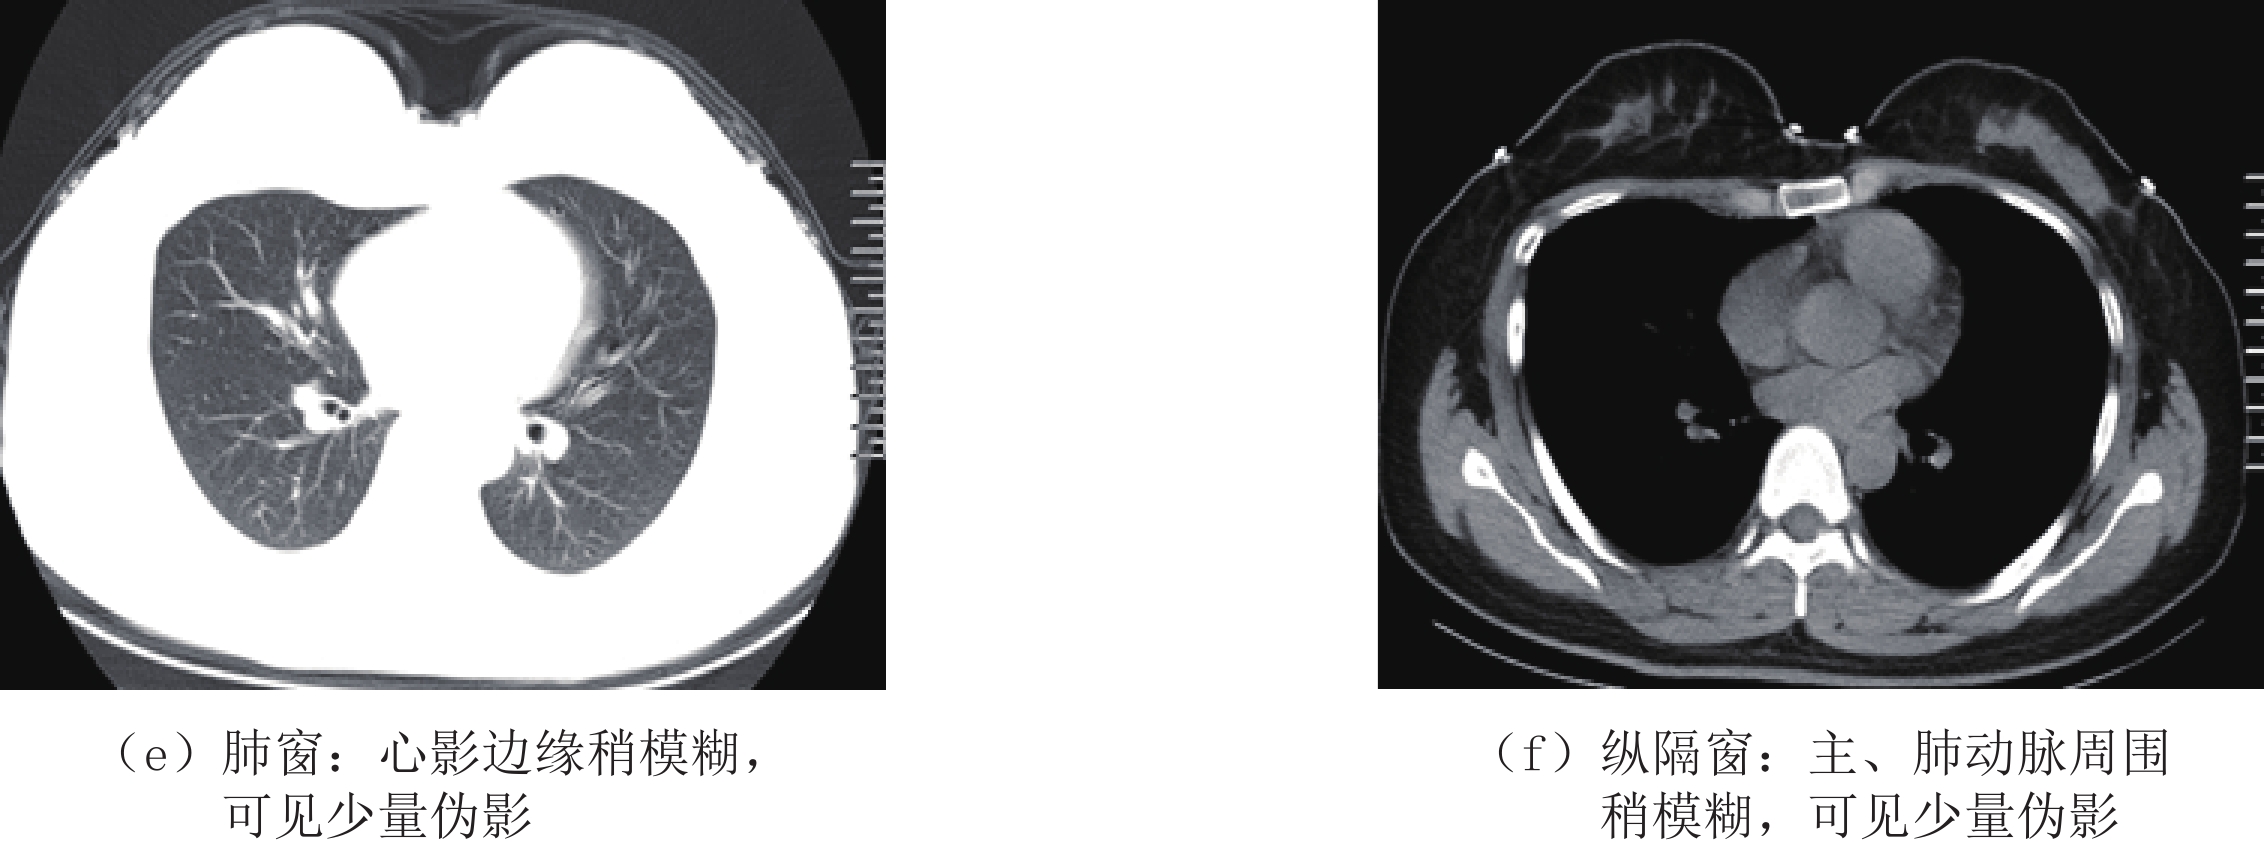

等级 图像质量 0分 未能显示正常结构 1分 大量伪影,正常结构中断 2分 边缘模糊,可见中等量伪影 3分 边缘稍模糊,可见少量伪影 4分 边缘稍模糊,未见伪影 5分 边缘清楚,未见伪影 表 2 两组CTDIvol、DLP、ED比较

分组 主观评分 平均值 统计检验 5分 4分 3分 2分 1分 Z P 低剂量组 16(17.6%) 71(78.0%) 4(4.4%) 0 0 4.13±0.45 -0.963 0.336 常规剂量组 21(23.1%) 67(73.6%) 3(3.3%) 0 0 4.20±0.48 表 4 两组间客观评价结果